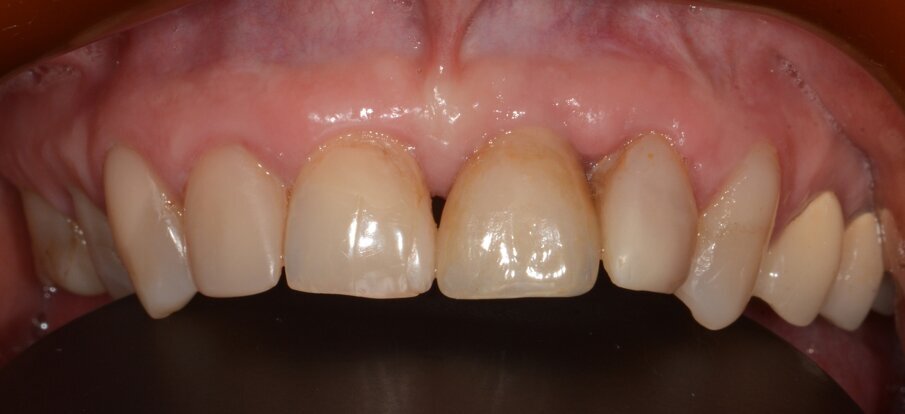

Case 1 was a patient who presented with deep pockets (9 mm), bleeding on probing and visible purulent effusion (Figs. 1–7) and was treated with a non-surgical protocol.

Fig. 1: Initial situation.

Fig. 7: Final results after three months. No sign of inflammation.